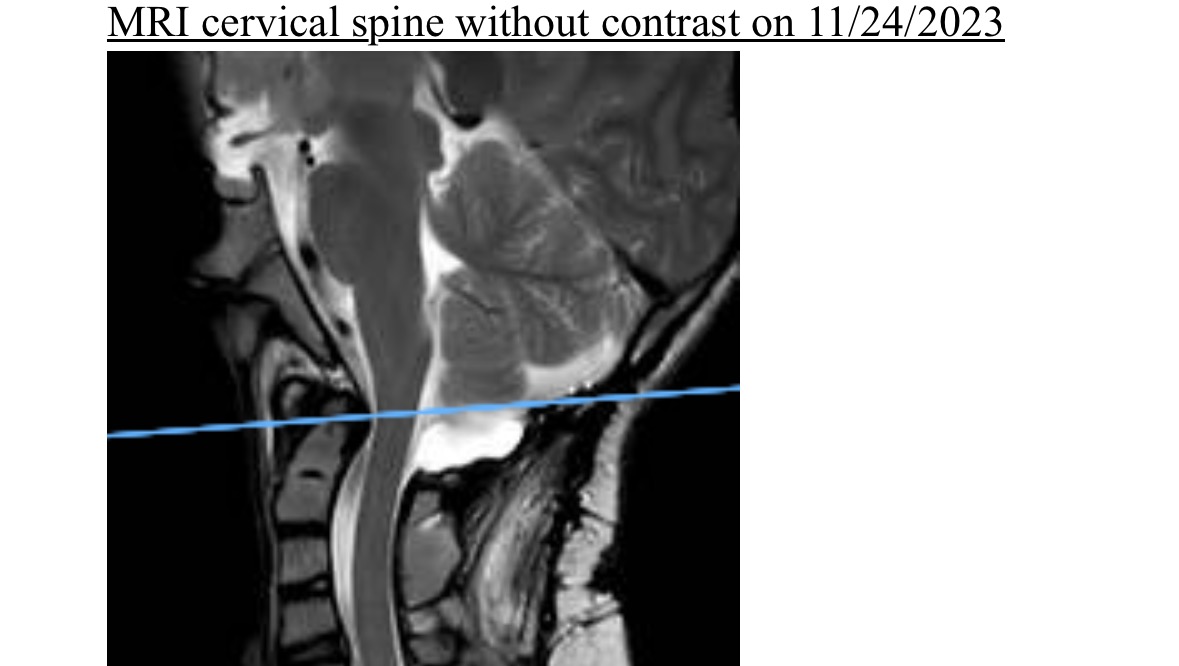

This past fall Connor started to decline rapidly. After several tests it was discovered that Connor’s spine was pressing on his brain stem causing instability and several debilitating symptoms. Due to Connor’s past this fusion will be extremely difficult and the type of surgery has never been done on a child before. His team in NYC has been practicing and are determined to give Connor his quality of life back. Connor is scheduled for surgery in NYC on April 10th with hopes of a sooner date once insurance is figured out. He is currently in a cervical collar full time to help relieve some on his symptoms.